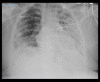

Coinfection with SARS-CoV-2 and Influenza A Virus in a 32-Year-Old Man

BACKGROUND There was a growing presumption that coinfection with severe acute respiratory syndrome coronavirus 2 (SARS-CoV-2) and another viral respiratory illness was nonexistent. Although there has been an increasing number of coinfection cases since the beginning of the SARS-CoV-2 pandemic, there is still a significant lack of information regarding the symptomatology, treatment, prognosis, and reasoning behind coinfection. This raises concern of the possibility of misdiagnosis or delay in treatment. CASE REPORT This case report discusses a coinfection of SARS-CoV-2 and Influenza A in a 32-year-old man to highlight that these viruses can coexist within the same patient. This patient unfortunately died of persistent respiratory failure after several days in the ICU. CONCLUSIONS Coinfection of SARS-CoV-2 and Influenza A can occur and lead to a poor prognosis.